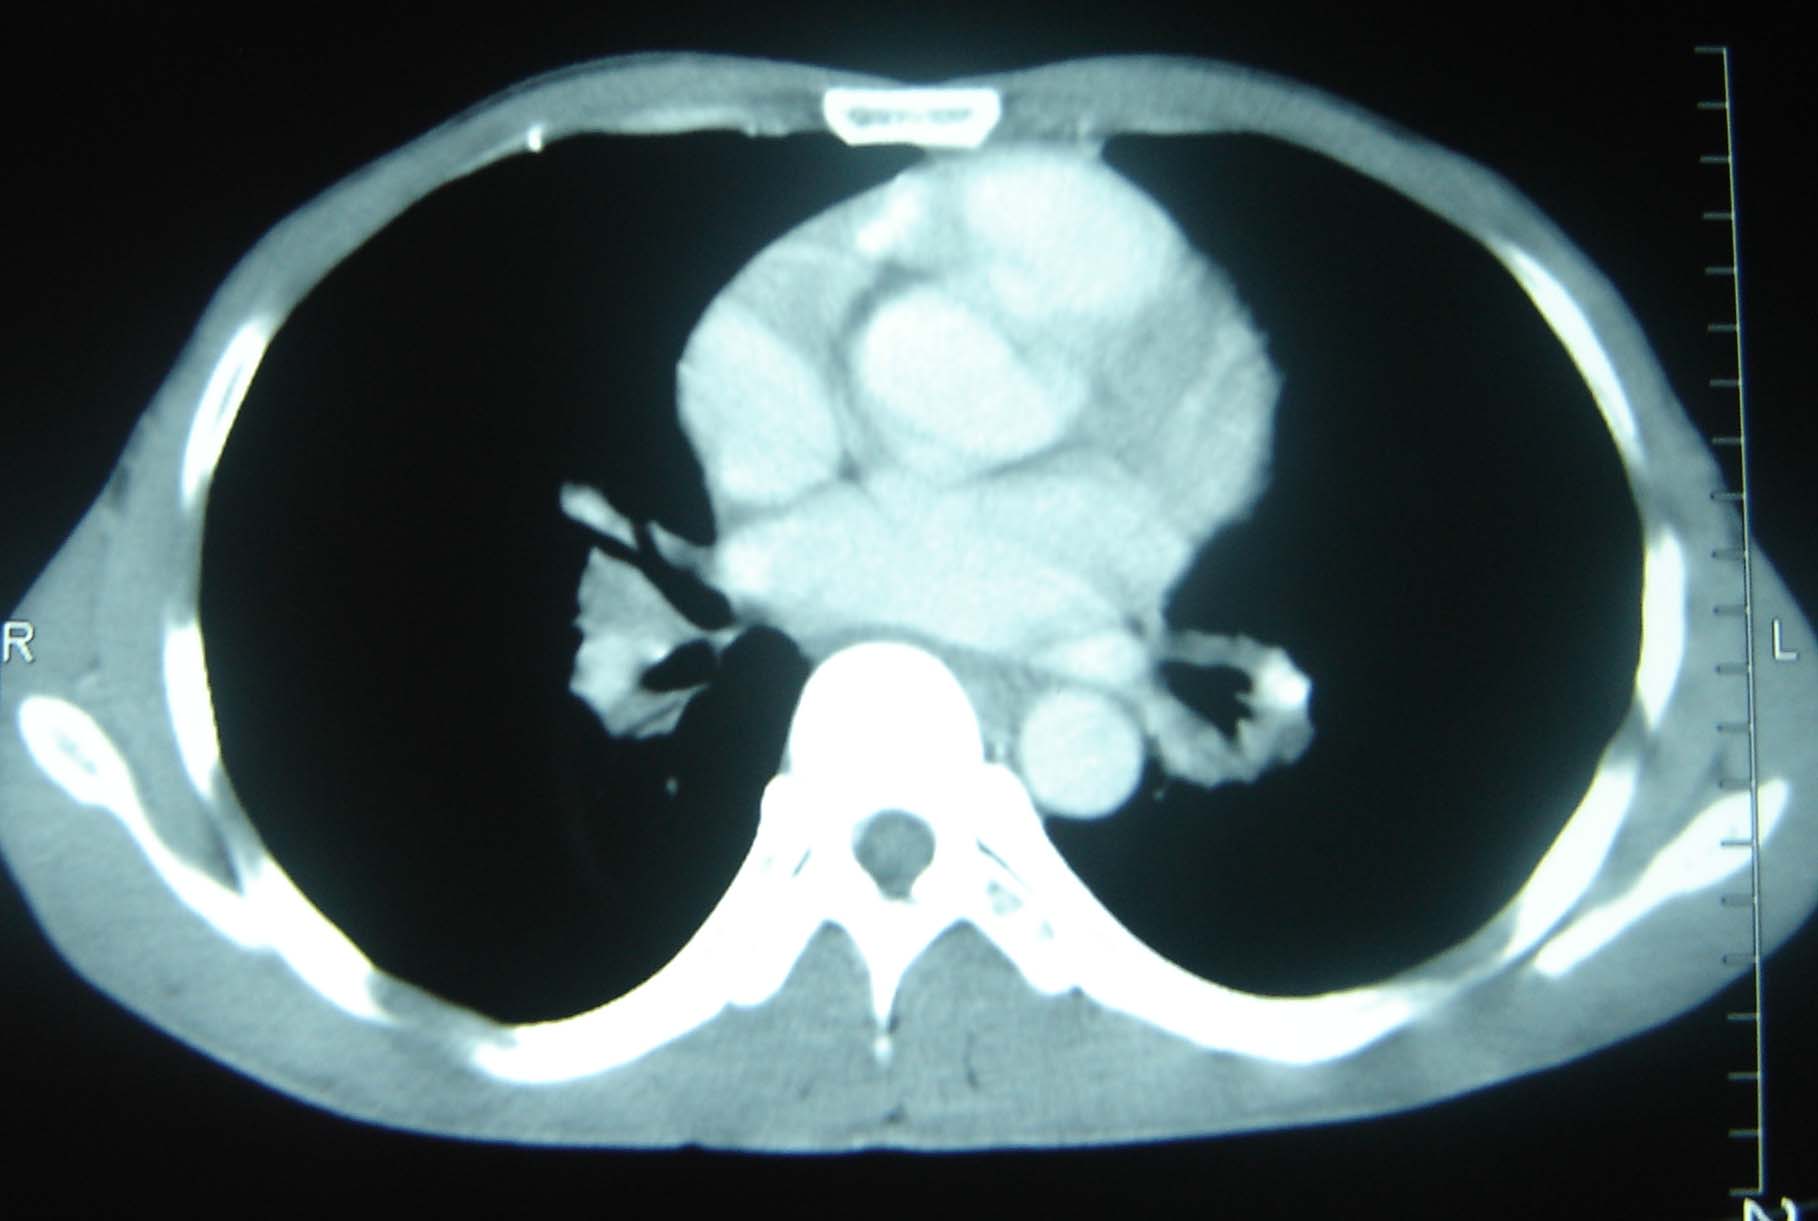

标题: CT25321:两肺多发结节 请会诊 [打印本页]

标题: CT25321:两肺多发结节 请会诊

男 、43岁,咳嗽胸痛,装修工,平时接触粉尘较多,有吸烟史10多年,纤维支气管镜检查未发现异常,胃镜、腹部b超检查亦未发现异常,颈部淋巴结活检未发现肿瘤细胞。

不能排除转移,如果不能找到原发灶,只有短期随访。

结节病?转移瘤?

1)考虑双肺及胸膜多发性转移瘤。2)肺气肿。